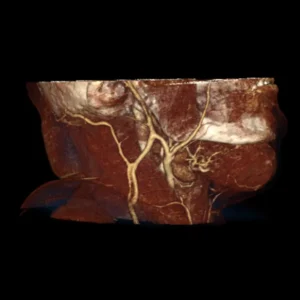

Malformaciones vasculares hemangionas

El diagnóstico y el tratamiento de las malformaciones arteriovenosas requieren un amplio conocimiento de esta rara enfermedad.

Son alteraciones congénitas del desarrollo vascular causando lesiones identificables de la piel mucosa y tejidos blandos, generalmente benignos, sus presentaciones clínicas varían conforme a la extensión y localización.